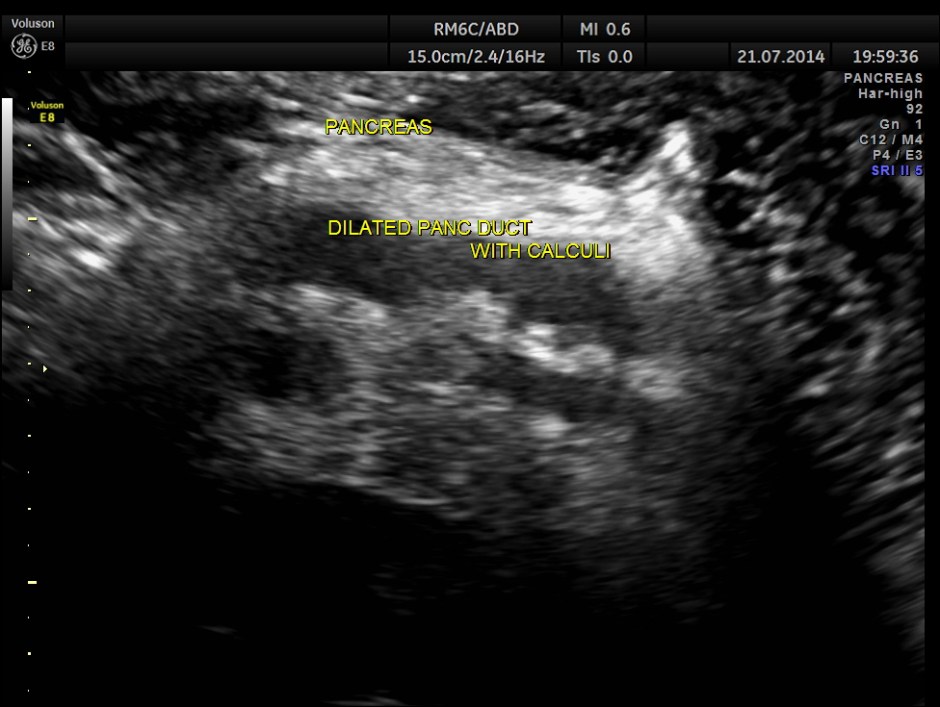

The following pictures show the pancreas.

Pancreatic duct is dilated prominently.

Pancreatic duct dilated.- 12.9 mms.

Pancreatic calculi are seen.